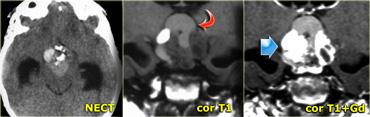

Hình bên trái là hình ảnh của một khối u trong bể trên yên.

Trên CT không tiêm thuốc cản quang (NECT), có thể thấy khối chứa vôi hóa.

Trên chuỗi xung T1W, có vùng tăng tín hiệu không ngấm thuốc (tức là thành phần nang).

Các thành phần khác có ngấm thuốc.

Khối u gây biến chứng não úng thủy.

Những đặc điểm này rất đặc trưng cho u sọ hầu (craniopharyngioma).

Hình bên trái là CT không tiêm và CT có tiêm thuốc cản quang của bệnh nhân nữ 33 tuổi với biểu hiện đau đầu dữ dội (nặng hơn vào buổi sáng), giảm thị lực và thu hẹp thị trường, kèm phù gai thị.

Tiếp tục xem hình ảnh MRI.

Lưu ý tuyến yên bình thường bị đẩy xuống dưới.

Điều này cho thấy đây không phải là u tuyến yên đại thể (macroadenoma).

Chẩn đoán một lần nữa là u sọ hầu (craniopharyngioma).

Chẩn đoán phân biệt bao gồm u tế bào hình sao (astrocytoma) và u màng não (meningioma).